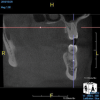

(10.) Tooth No. 31 in this 14-year-old patient does not exhibit caries. It is a “ghost tooth.” The lack of a periapical pathosis, the location of the tooth relative to the inferior alveolar nerve, and the development of tooth No. 32 are all visible in the CBCT image. These factors will aid the clinicians in developing a treatment plan to deal with this unusual internal resorption case.

Figure 10

Identifying the shape and location of the roots of teeth to be removed is critical to performing safe exodontia. Some clinicians virtually deconstruct teeth using CBCT images prior to actually sectioning and removing them. Being able to recognize pathoses and differentiate affected structures from normal structures is key in deciding what the treatment should be and when that treatment should be initiated (Figure 8 through Figure 10). The arena of the oral surgeon is larger than that of many general practitioners, involving the sinuses and condyles and other considerations in and around the entire mandible and maxilla. Certain fractures and other conditions that some general practitioners feel uncomfortable treating are often referred for evaluation and treatment by an oral surgeon. Because of this, oral surgeons require the most accurate and complete diagnostic information available. The American Academy of Oral and Maxillofacial Radiology recommends that "cross-sectional imaging be used for the assessment of all dental implant sites" and has stated that "CBCT is the imaging method of choice for gaining this information."18